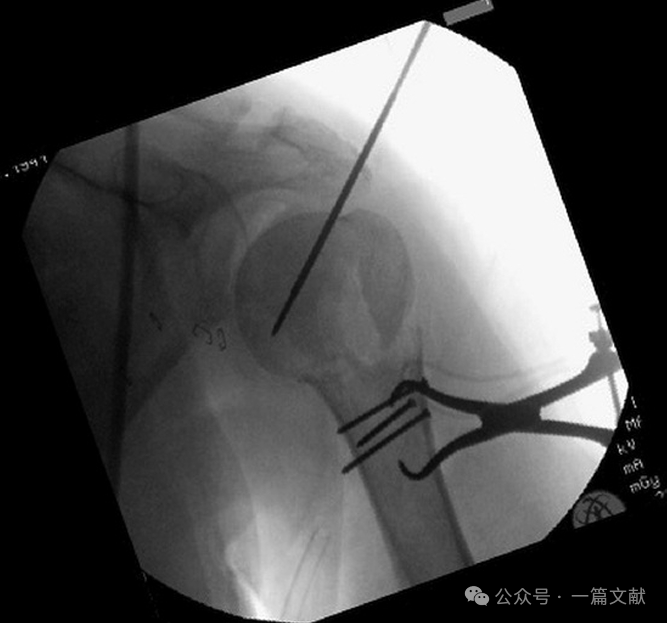

三,标准肩关节正位片(Grashey 位):

将C臂机内旋30°,与盂肱关节相匹配。此视图最能清晰显示肩关节的轮廓。可以清晰观察肱骨头的形态和内侧肱骨矩的复位情况,并可用于评估术中螺钉长度以免穿透关节面。如下图:

体位与拍摄角度:C臂机内旋30°。